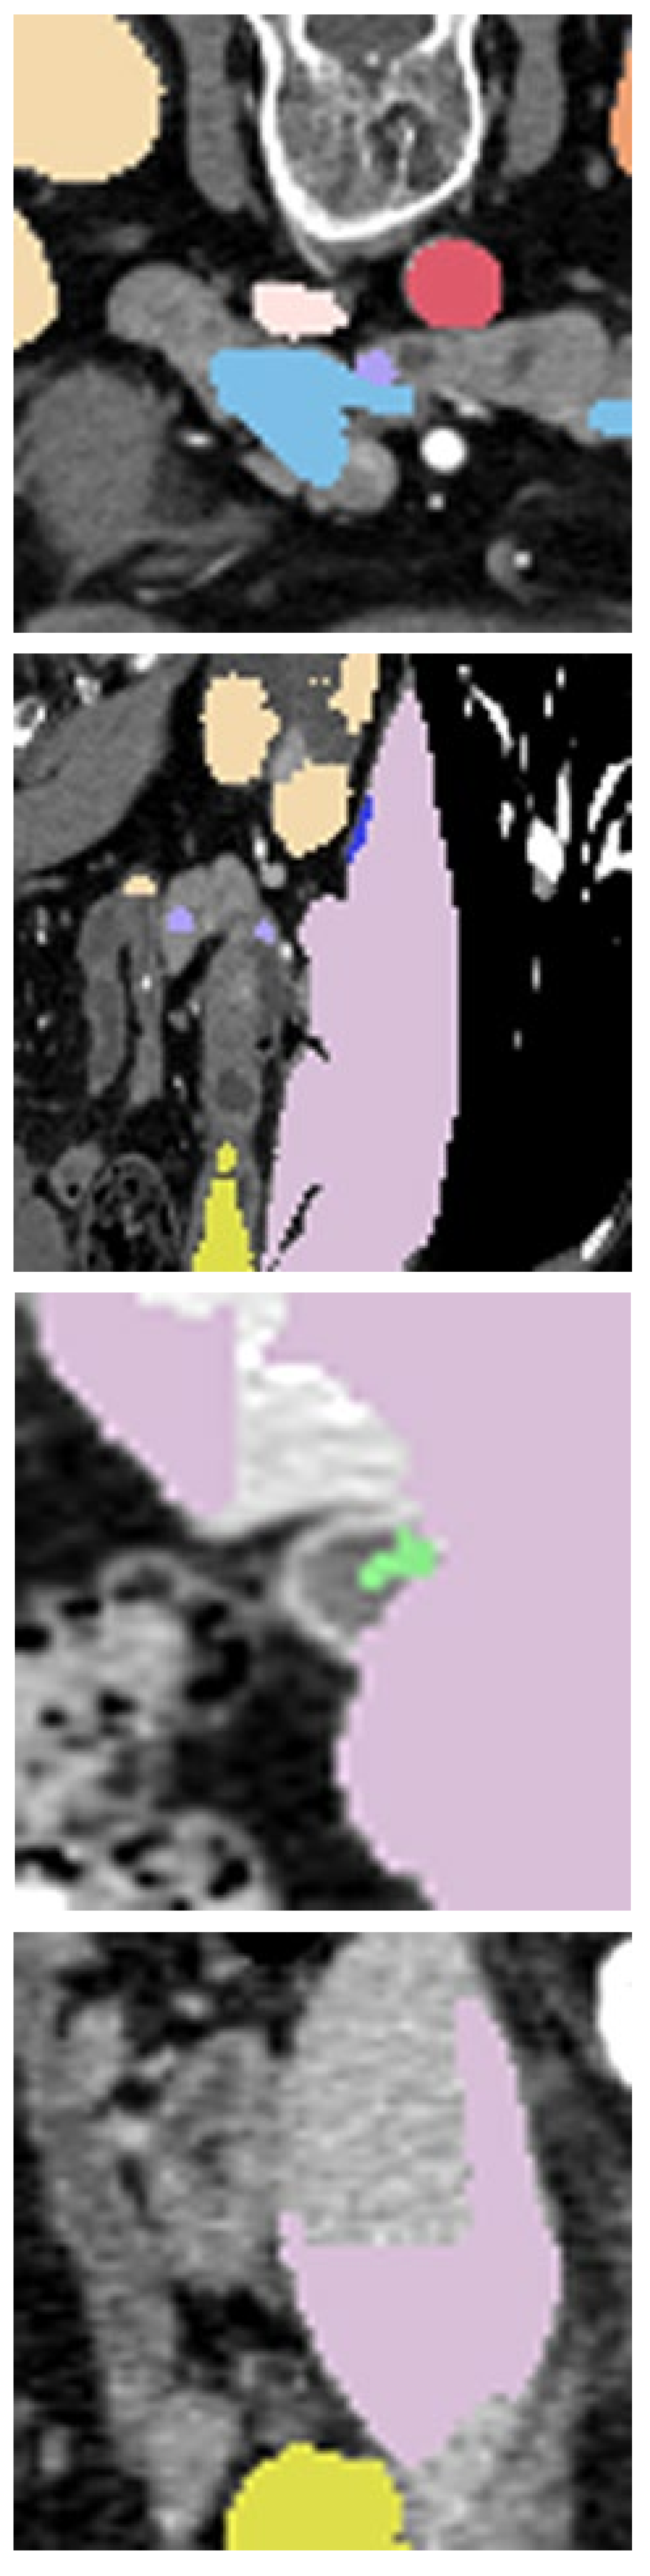

Refer to caption

Figure 2: Examples of textual anatomical knowledge and their corresponding 3D visualizations. (a)-(d) indicate the inter-organ spatial relationship priors for the duodenum. (e)-(f) indicate the organ shape priors for the stomach. The font color corresponds to the organ in the 3D visualization.

The anatomical structure of the multi-organ in human body holds valuable prior information, such as inter-organ spatial relationships and organ shape priors. For instance, the duodenum typically exhibits fairly consistent positional relationships with adjacent organs such as the pancreas, stomach, liver, gallbladder, and kidneys. As illustrated in Fig. 2 (a) - Fig. 2 (d), especially in Fig. 2 (b), the duodenum lies posterior to the stomach and anterior to the inferior vena cava and aorta. Due to its relatively small voxel proportion, segmentation models frequently overlook the duodenum. Consequently, a key question is how to leverage its inter-organ spatial relationships (especially its relationships with larger organs, like stomach, kidney, etc.) to improve segmentation performance for this challenging category. Furthermore, as noted in [40], in class-imbalanced semi-supervised multi-organ segmentation tasks, the model not only yields poor segmentation performance for categories with a small voxel proportion, but also struggles with organs that have larger voxel proportions yet complex morphology, such as the stomach. Another question is how to flexibly and robustly inject morphology and shape prior into the model to improve the segmentation accuracy for categories with complex morphology.

We propose an anatomy-aware framework that integrates two complementary priors: (1) Inter-organ Spatial Guidance, where leveraging consistent positional relationships between small and adjacent large organs to redirect model attention to underrepresented regions. (2) Shape-Aware Regularization, where encoding organ shape priors to constrain segmentation outputs to more anatomically plausible forms. We first employs GPT-4o to generate textual descriptions of these anatomical priors. Fig. 2 shows some textual descriptions and visualization of these priors. The detail of this Textual Anatomical Knowledge (TAK) Generation process is illustrated in Sec.3.2. These robust and generic textual anatomical knowledge are then encoded as adaptive parameters in the segmentation head to refine feature decoding. Simultaneously, a contrastive alignment module ensures consistency between visual features and anatomical constraints, bridging language-derived knowledge with pixel-level predictions. This anatomy-guided segmentation process is illustrated in Sec.3.3. The overall framework is illustrated in Fig. 3.